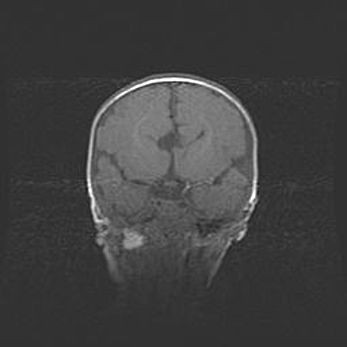

Подострая гематома правой гемисферы мозжечка.

Наружная гидроцефалия.

Возраст: 15 дней

Вес: 3100 г

Пол: женский

Окружность головы: 37 см

Срок гестации: 35-36 недель

При открытой наружной форме гидроцефалии у новорожденных расширяются и переполняются субарахноидные пространства.

Кровоизлияния в мозжечок имеют две клинико-анатомические формы: полушарные гематомы и кровоизлияния в червь.

К появлению этой патологии может привести: повреждения головного мозга, возникающие в результате асфиксии и гипоксии плода при беременности, или травмы во время родов. Редко гематома мозжечка может быть результатом первичной коагулопатии и сосудистой мальформации, диссеминированном внутрисосудистом свертывании, изоиммунной тромбоцитопении.